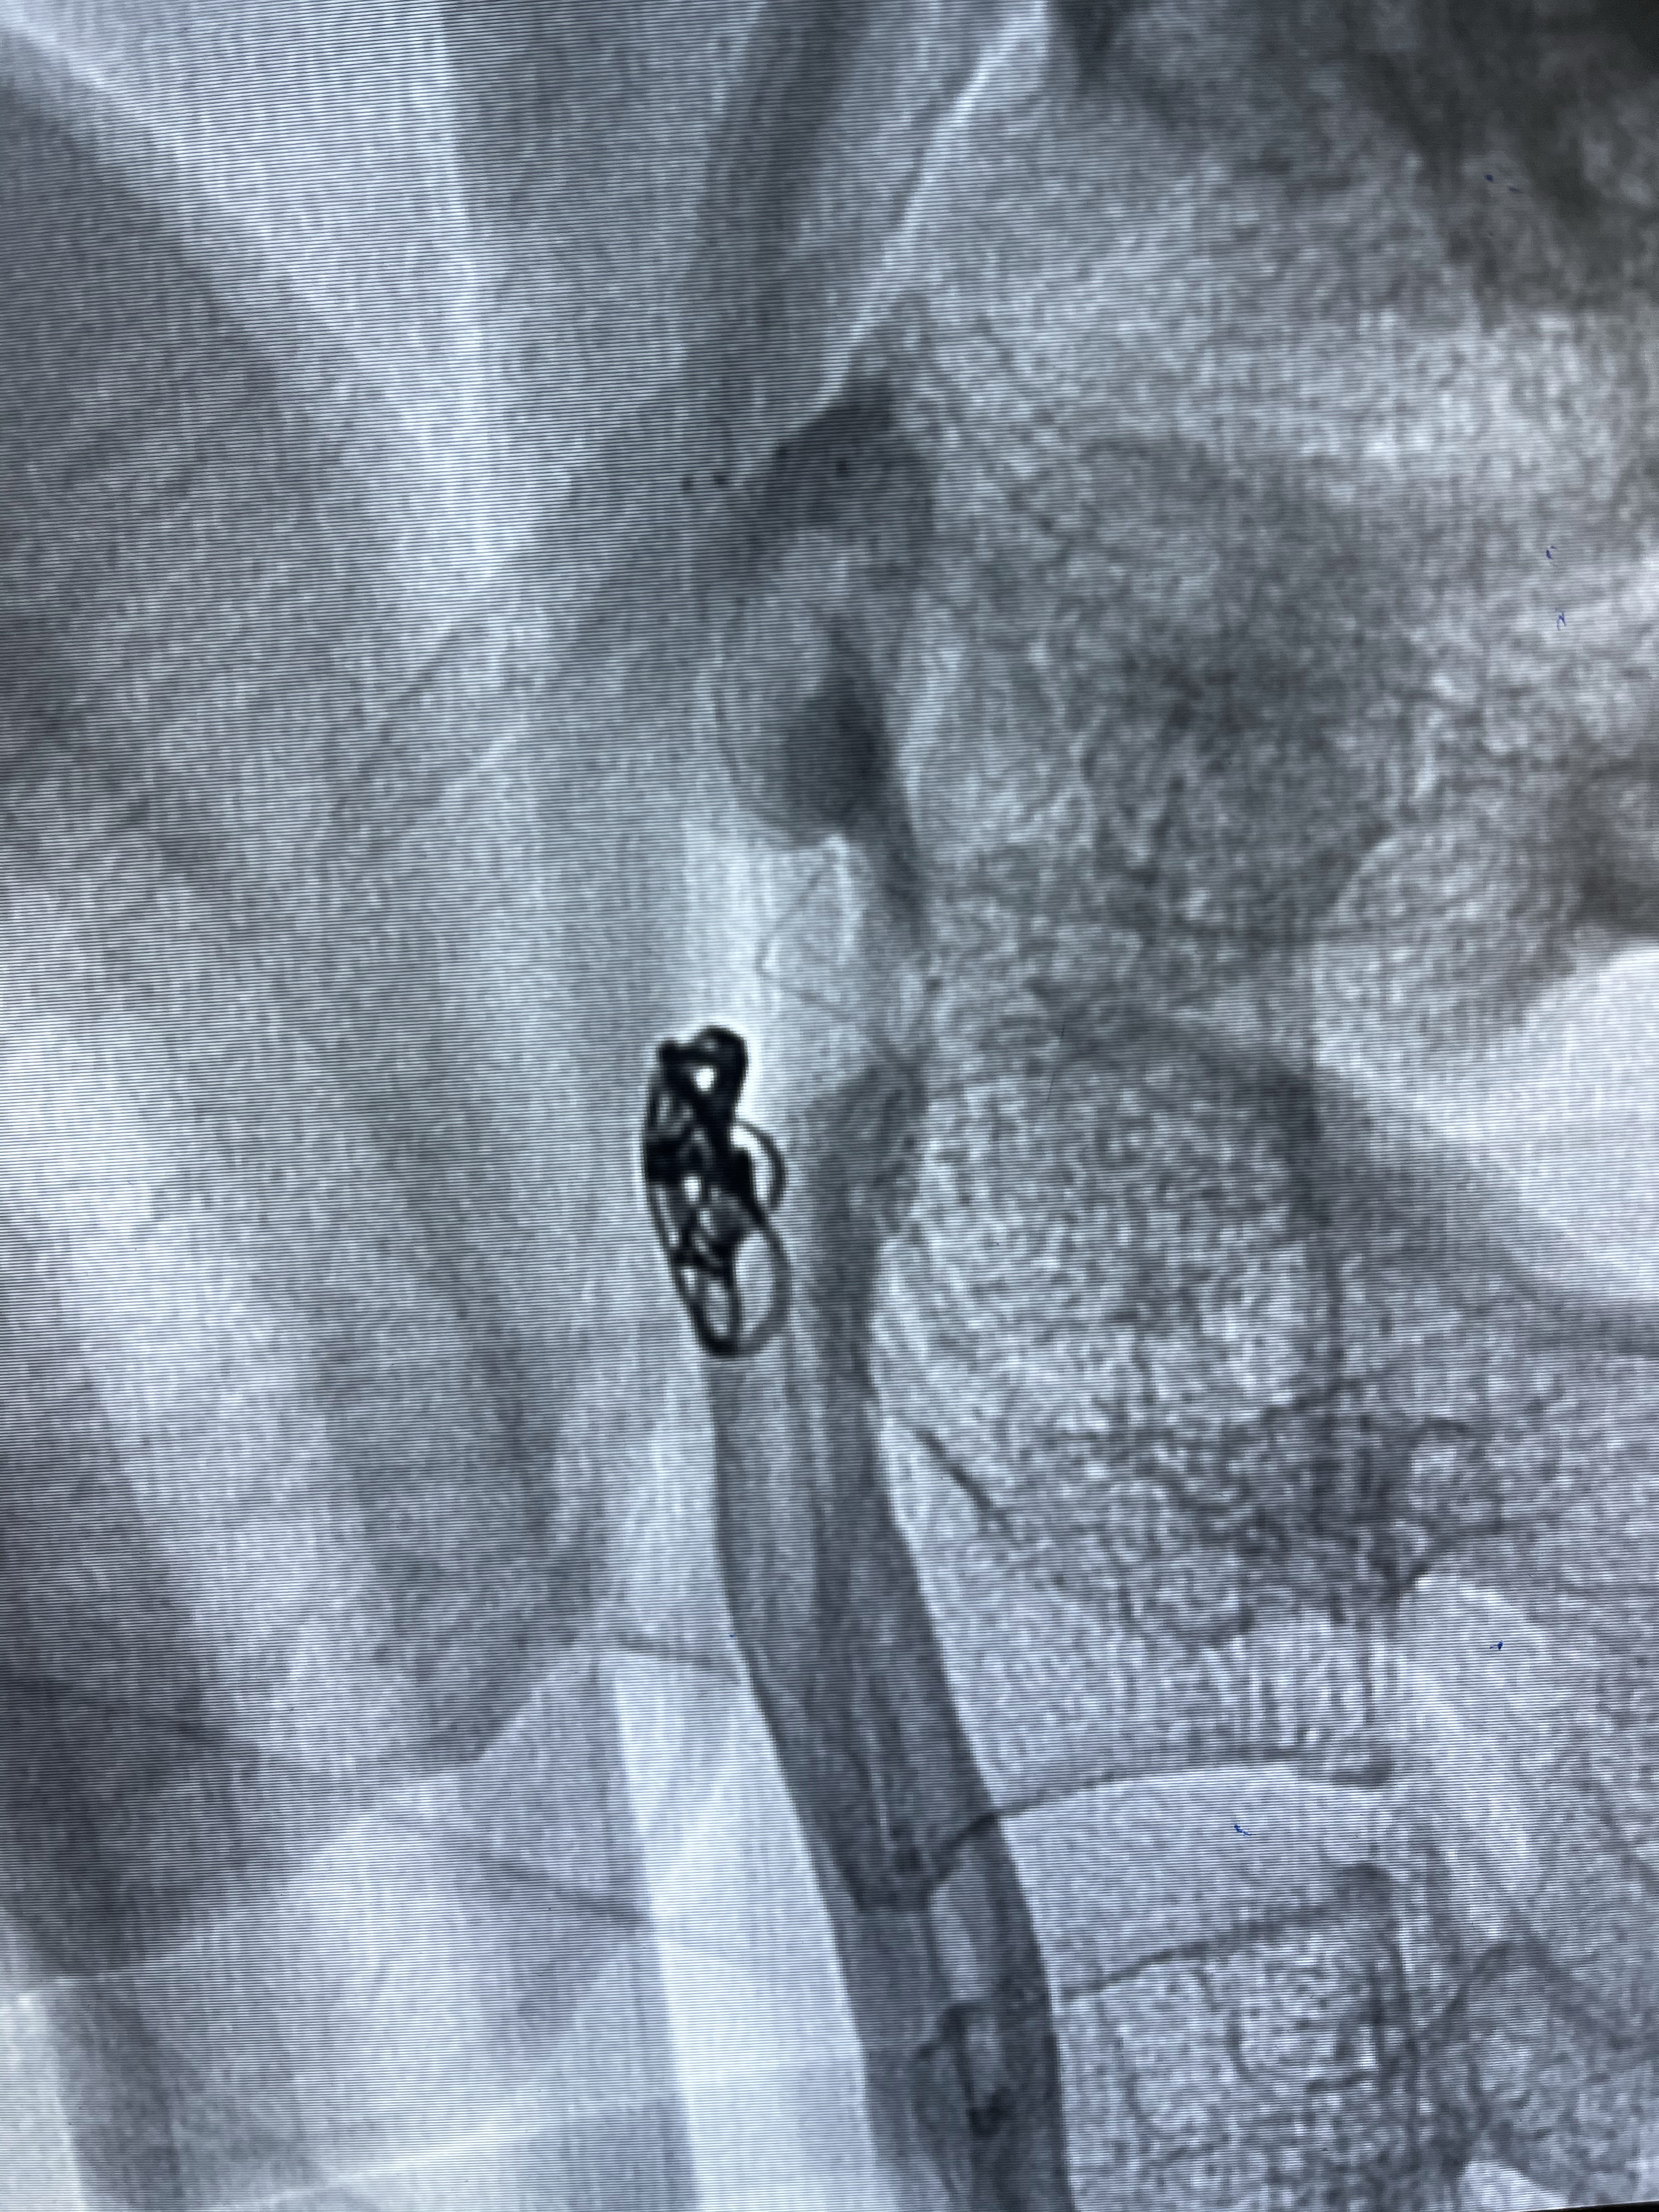

8mm-40cm微弹簧圈成篮

即刻造影

支架到位